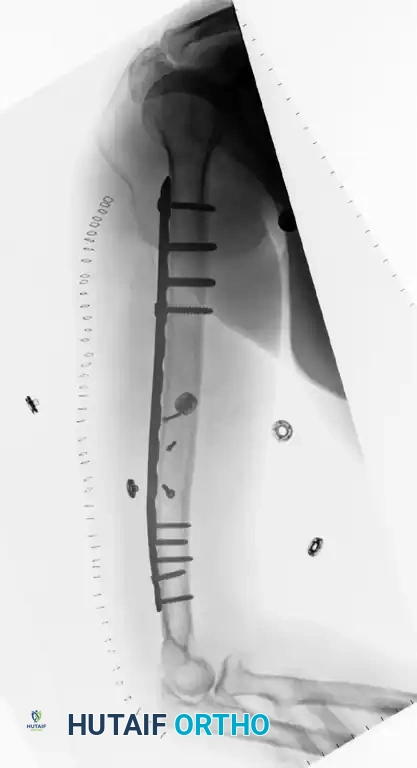

Figure 57-38 A: Segmental shaft fracture with extension into the proximal humerus.

Figure 57-38 B: Long plate utilized to obtain secure fixation across the segmental defect.

Figure 57-38 C: Lateral radiographic view demonstrating secure fixation with a long plate.